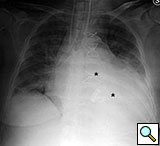

Figure 11. Fourteenth postoperative day image showing sternal wire migration in the caudal sternum segment (*).

Figure 12. Postoperative sternal reconstruction showing sternal fixation with DSS (2 and 3 units in the right and left hemisternum, respectively